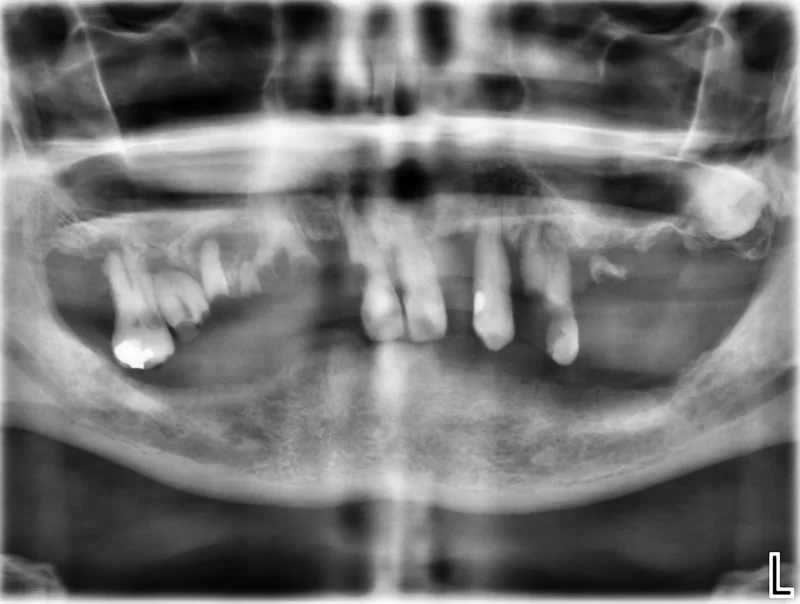

Case 37 – Implants

Upper complete denture and lower implant retained complete denture